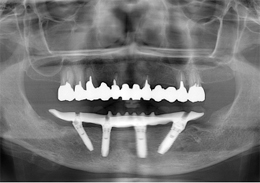

下顎のALL-ON-4①(下の歯のオールオンフォー)

- もともと入っているインプラントの周りが腫れ、残りの歯も動いているので力が入らない

- 下顎右側に以前埋入したインプラントの撤去を行い、歯周病の進行が著しかった残存歯の抜歯を行うと同時にインプラントの埋入を行い、当日仮歯を装着した

- 下顎ALL-ON-4:4,000,000円(税別)

- 6ヶ月